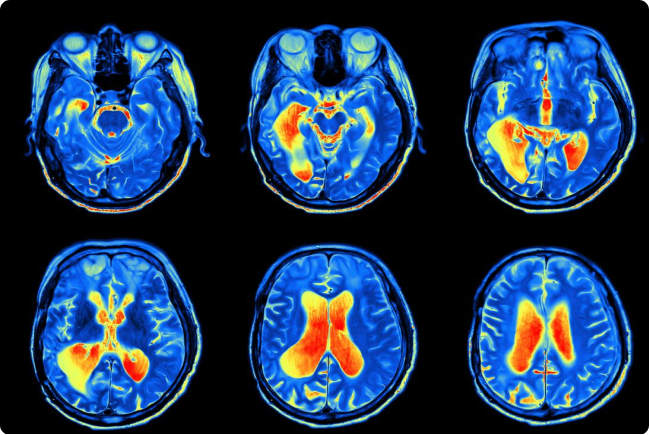

Påverkan på hjärnan

Forskning indikerar att luftföroreningar kan bidra till inflammation i hjärnan och påverka nervsystemets funktion. Detta kan i sin tur kopplas till försämrat psykiskt välbefinnande, koncentrationssvårigheter och humörförändringar.